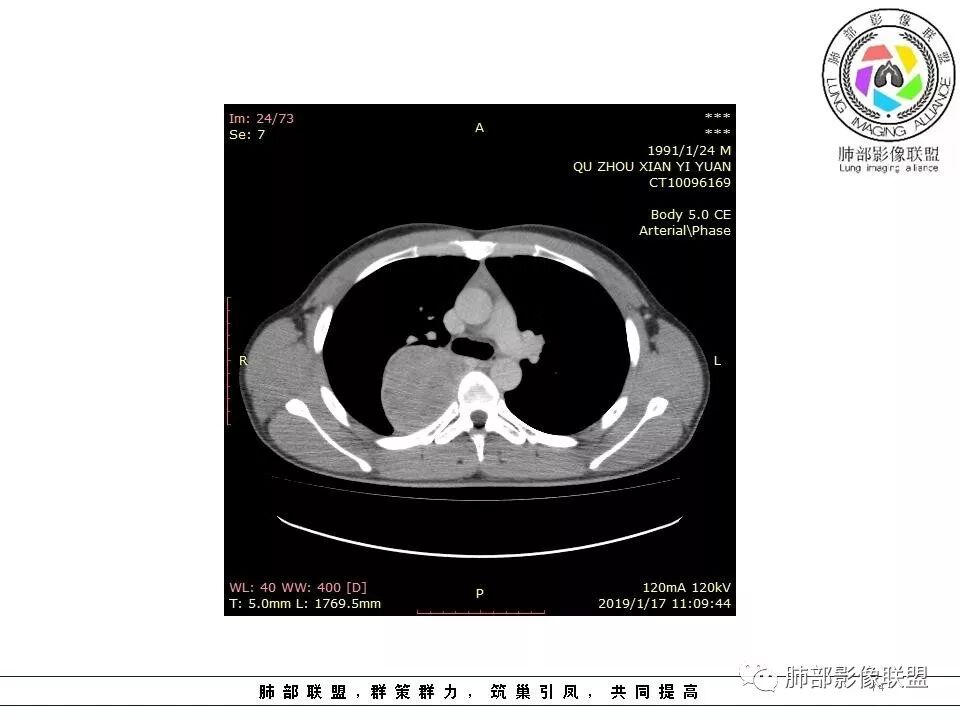

右后纵膈脊柱旁软组织占位,形态规则类圆,边缘光整,肺组织受压,胸膜尾,肋间动脉供血。中度不均匀延迟强化。

右后纵膈脊柱旁软组织占位,边界清晰,光整,肺组织受压。胸膜被掀起,肋间动脉供血,中度不均匀延迟强化。考虑神经鞘瘤,不除外纤维瘤

右后纵膈脊柱旁软组织影,与纵隔结构分界不清,形态规则类圆,边缘光整,肺组织受压,胸膜尾,肋间动脉供血。肺动脉推移,中度不均匀延迟强化。考虑神经来源,神经鞘瘤,神经纤维瘤二者不易鉴别。

青年男性,间断胸痛;右侧脊柱旁可见一类圆形软组织密度影,密度欠均匀,增强扫描呈轻中度持续强化,邻近肺组织及肺动脉推移,可见肋间动脉供血,部分胸膜下脂肪可见,部分层面似见与右侧椎间孔相连。考虑后纵隔神经源性肿瘤。

1.右上胸内脊柱旁类圆形肿块,质地似乎比较坚实,密度稍显不均,但未显示明确的坏死。

如此密度形态的病灶位于肺边缘首先应当想到孤立性纤维瘤,可相邻胸膜未见明显的异常强化和胸膜方向延伸。

2.肋间动脉病供血也提示肿块来自后纵隔?